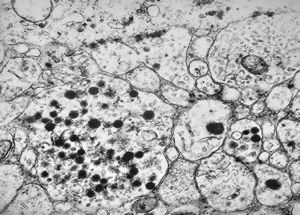

F, 45y. | carcinoid … liver metastasis